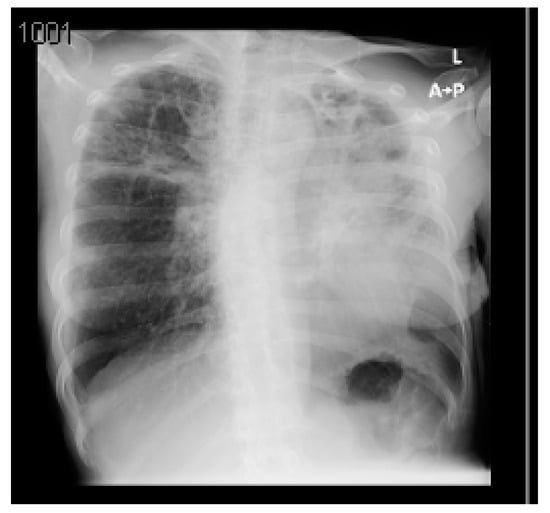

A summary of the patient’s CXR and lab investigations’ findings are demonstrated in Figure 3 and Table 3, respectively.

An ACT scan of the chest was completed to verify the findings of the CXR. The CT scan revealed large cavitary lesions with septations involving both lungs more severely at the upper lobes bilaterally. They were associated with traction bronchiectasis, bronchial wall thickening, fibrotic changes and tri in buds.

Multifocal patches of ground-glass opacities were seen involving both lower lobes, associated with a crazy-paving appearance. Mucous secretions were seen in the trachea, right main bronchus and right bronchi. Interstitial septal thickening was noted with diffuse nodular changes.

Figure 3. Posteroanterior chest X-ray (CXR) of the third case. The CXR shows diffuse bilateral reticular infiltration, mainly in the middle zones with bilateral apical cavitary lesions. The cardiac shadow and configuration are shaggy but generally show no abnormality, and the costophrenic angles are clear.